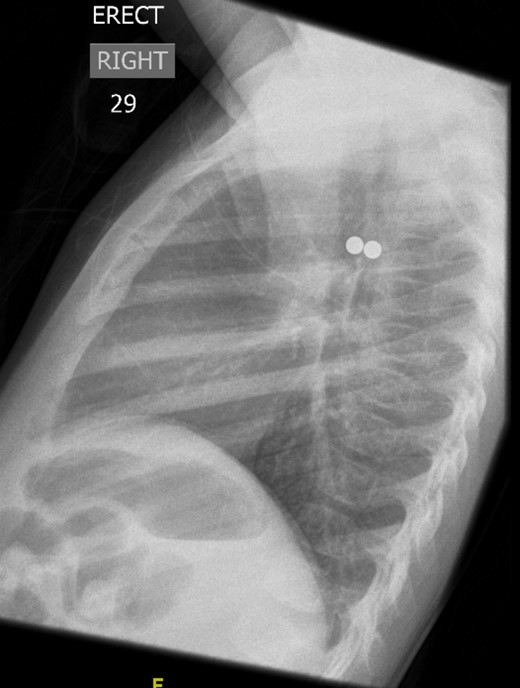

A ventilating bronchoscopy was performed by the otolaryngology team where the FB was found to be stuck to the posterior wall of the left main bronchus. The FB was left in-situ. After the operation, a lateral CXR (Fig. 3) illustrated the metallic FB appeared to be two spherical balls, with the anterior one in the left main bronchus and the posterior one in the oesophagus. A subsequent further history from the parents suggested these were from the older sibling’s toys.

Lateral CXR showed the metallic foreign body to be two spherical balls, with the anterior one in the left main bronchus and the posterior one in the oesophagus.